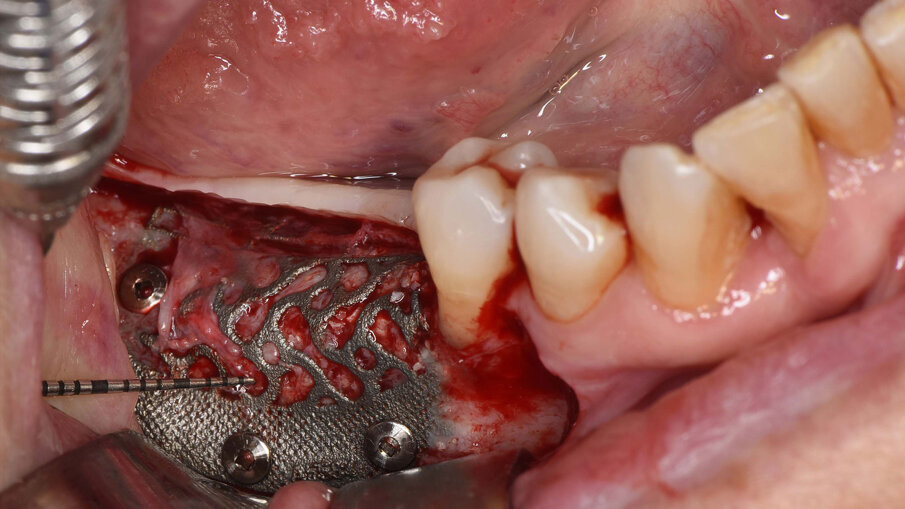

Il prelievo di osso autologo particolato è stato eseguito dal ramo mandibolare, distalmente alla zona da ricostruire mediante uno scraper (SafeScraper Twist, META). La griglia è stata provata nel sito ricevente per verificarne la congruità. Ogni residuo di tessuto connettivo è stato rimosso; per aumentare la rivascolarizzazione precoce del materiale innestato, sono state eseguite delle perforazioni della corticale ossea del sito ricevente (Figg. 3, 4). Dopo preparazione dei siti implantari, sono stati posizionati due impianti “root form” e “bone level” in zona 4.6 e 4.7 (4.1 x 8 mm; Straumann) usando una dima chirurgica. La griglia è stata quindi riempita con un mix di osso autologo ed eterologo (Geistlich Bio-Oss, Gestlich Pharma) in rapporto 1:1, è stata fissata con 3 micro-viti in titanio di 1.4 mm di diametro (MC Bio) ed è stata ricoperta con una membrana riassorbibile (Geistlich Bio-Gide, Gestlich Pharma; Figg. 5, 6). La sutura è stata eseguita per prima intenzione (Fig. 7).

Fig. 5_Visione intra-operatoria della griglia riempita con un mix di osso autologo particolato prelevato dal ramo mandibolare e osso eterologo in rapporto 1:1 e fissata mediante 3 viti in titanio di 1.4 mm di diametro e dopo inserimento di due impianti osteointegrati.

Fig. 6_Visione intra-operatoria della membrana riassorbibile (Geistlich Bio-Gide) posizionata sopra la griglia.

Figg. 9a-9c_Foto intra-operatoria durante la rimozione della griglia in titanio che evidenzia l’incremento osseo ottenuto e l’assenza di perdita ossea al di sotto della griglia.